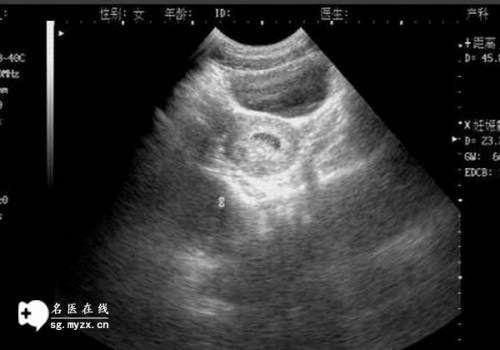

輸卵管堵塞是一種關(guān)于生殖健康的常見(jiàn)問(wèn)題,因?yàn)樗赡苡绊懙缴芰Α]斅压芏氯赡軙?huì)導(dǎo)致不孕不育。因此了解輸卵管堵塞的原因和預(yù)防措施,以及如何處理它們,是非常重要的。

輸卵管堵塞的原因可以分為內(nèi)部原因和外部原因。內(nèi)部原因是指輸卵管的結(jié)構(gòu)本身導(dǎo)致的,比如輸卵管的萎縮、內(nèi)膜發(fā)育不良、輸卵管結(jié)石等,都可能導(dǎo)致輸卵管堵塞。外部原因一般是指外部因素導(dǎo)致的,比如宮外孕、宮腔粘連、外傷等,這些都可能會(huì)導(dǎo)致輸卵管堵塞。

輸卵管堵塞的癥狀一般比較模糊,常見(jiàn)的癥狀有疼痛、反復(fù)發(fā)熱、反復(fù)腹痛和經(jīng)期不規(guī)律等,這些癥狀可能會(huì)讓人感到困擾。

當(dāng)發(fā)現(xiàn)輸卵管堵塞時(shí),應(yīng)及早就醫(yī),并根據(jù)病情選擇適當(dāng)?shù)闹委煼椒āMǔG闆r下,醫(yī)生會(huì)根據(jù)患者的具體情況,采用手術(shù)、藥物或血液療法來(lái)治療輸卵管堵塞。有時(shí)醫(yī)生會(huì)采用體外受精的方法來(lái)解決輸卵管堵塞問(wèn)題,以便讓患者成功懷孕。